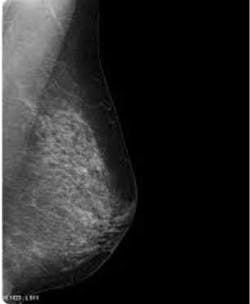

The risks and benefits of screening mammography continue to warrant considerable debate and attention. Randomized controlled trials (RCTs) conducted from the 1960s to 1980s showed that screening mammography reduced breast cancer mortality.(1) But these studies were conducted in a period when breast cancer treatments were less effective and women were not as aware of breast cancer and its causes and treatments. This study looked at RCTs comparing mammographic screening with no mammographic screening.

The conclusion was that the 25-year collective mortality from breast cancer was comparable among women in the mammography and no-mammography groups, and these findings did not differ with age. Within 15 years of baseline, over 106 cases of breast cancer were identified with screening mammography. Therefore, 22% of screen-detected cancers (106/484) represented overdiagnosed breast tumors.(3) An editorial in the British Medical Journal (BMJ) suggests that long-term follow-up does not support breast cancer screening in women under the age of 60.(4) The authors of the editorial agree with Miller and colleagues that the justification for screening by mammography should be reassessed by policymakers.

The outcomes of the Canadian study support those of other studies of breast cancer screening.(5,6) These studies propose that screening's influence on the decline in breast cancer mortality is exceeded by improvements in treatment. Also, the benefits of screening mammography are smaller and the harms associated with overdiagnosis are greater than have been previously appreciated. Mammograms are expensive and have high rates of false-positive findings.(7,8) For years, we’ve been told that mammograms can save lives. The feeling of getting an annual mammogram is comforting. So for many women this new information will be confusing, and others will be very suspicious. Some experts suggest encouraging patients to follow the 2009 U.S. Preventive Services Task Force guidelines which says that average-risk women should be screened every two years beginning at age 50.(9)